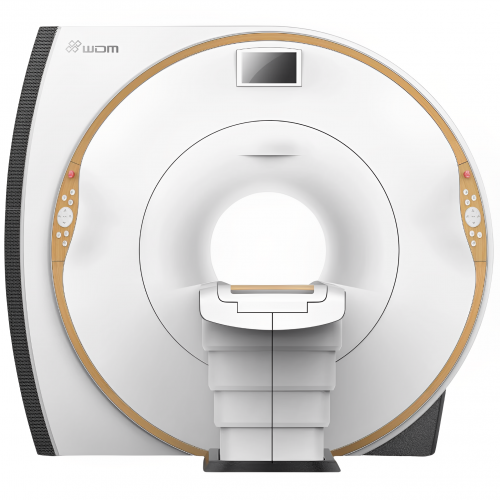

CR Wandong recently released its i_Magnate 1.5T optical superconducting MRI system. This system uses the most advanced optical technologies for transmitting radio frequency signals and parallel image processing technology over 8-32 channels. This ensures excellent image quality and high scanning speed.

The new i_Magnate 1.5T has a large Open Bore design and a very short system. This can give you a feeling of comfort when scanning. Thanks to the new mobile device management technology and digital image processing platform, you can enjoy a wonderful experience of intelligent and efficient work.

Main function